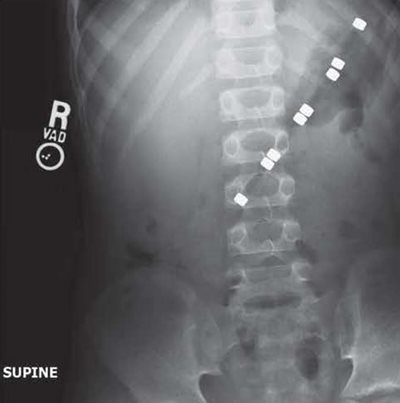

Figure 1

An obstructive abdominal x-ray series was obtained (left). The interpretation read: "Supine and upright views of the abdomen show an elongated rod shaped radiopaque structure measuring maximally 12 cm. in length and about a centimeter in width which lies obliquely within the stomach. It has 8 dense radiopaque elements. The bowel gas pattern is normal. The osseous structures are intact."